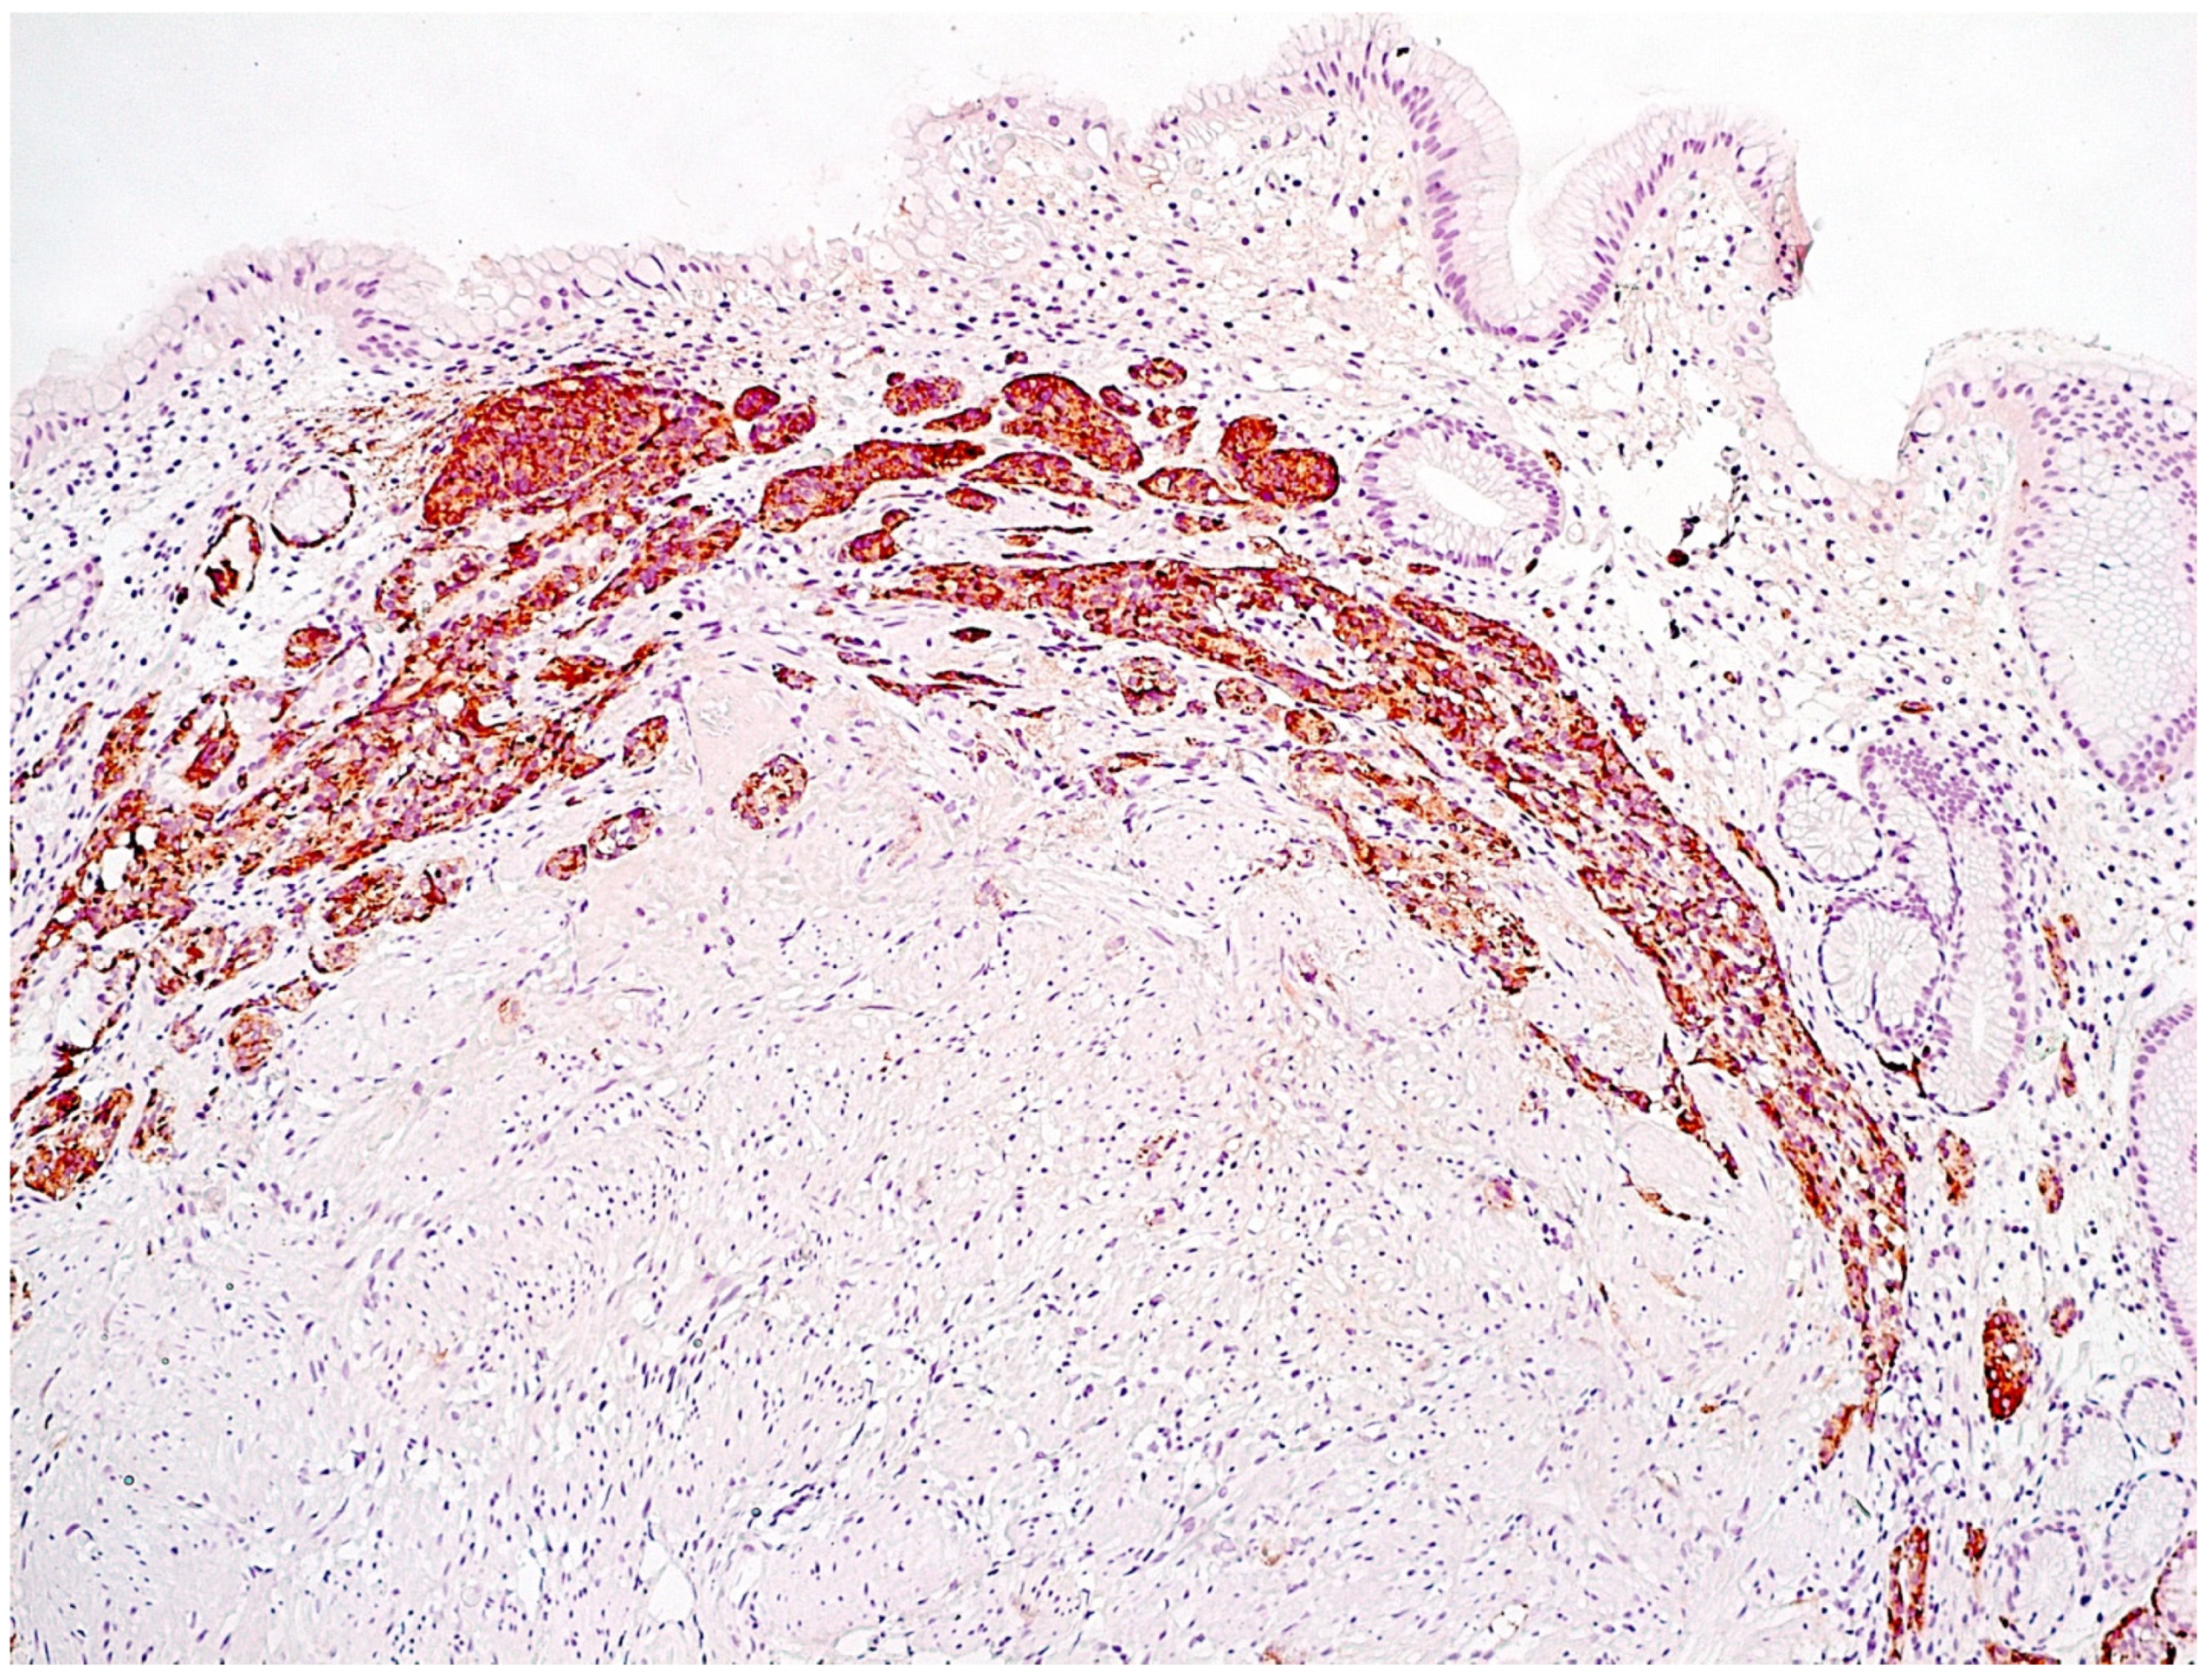

- Adenomatous (adenomatoid) hyperplasia. The presence of an aggregate of five or more clusters (Figure 5).